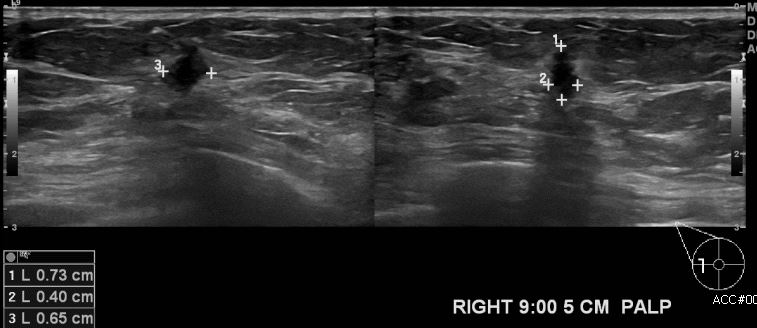

상기환자 건강검진상 이상 소견으로 내원하신 50대 여성분으로 우측 9시 방향에서

5 cm 떨어진 거리에 만져지는 멍울 조직검사 시행하여 우측 침윤성 유관암 진단되었습

니다.